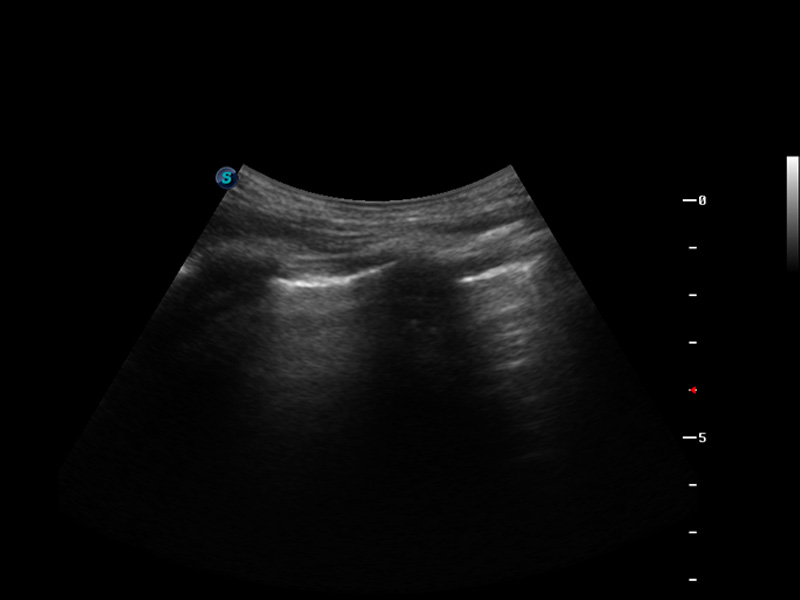

造影成像